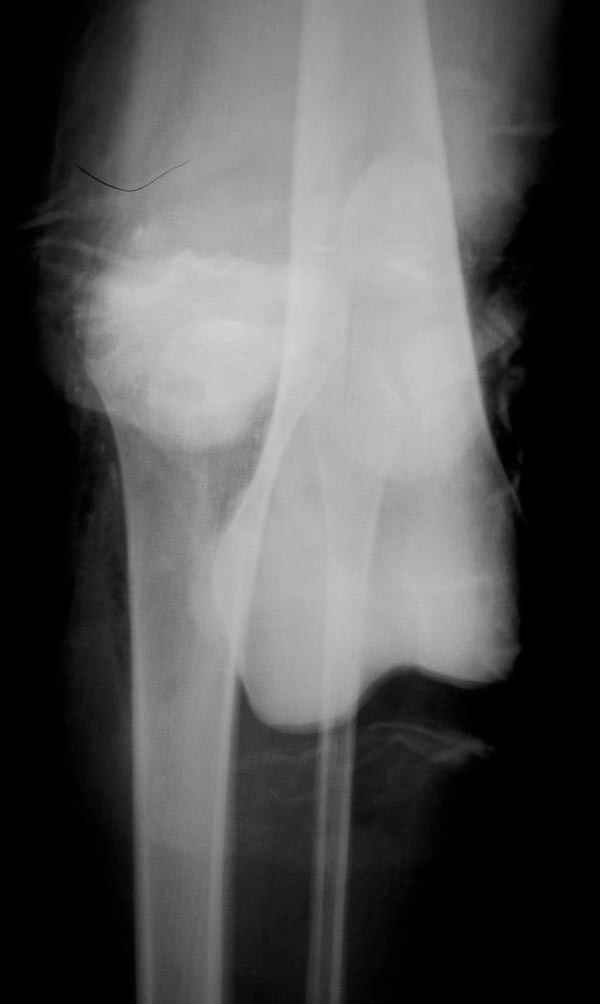

В приемное отделение поступает больная 22 лет, во время аварии ремень безопасности не был пристегнут, в крови большое количество кокаина.В приемном срочная интубация и седация, сделаны снимки.Диагностирован: открытый вывих левого коленного сустава.

Заключительный диагноз: Открытый вывих коленного сустава, перелом надколенника, разрыв собственной связки надколенника

Сегодня досылаю остальные снимки, которые не прошли вчера. Как вчера писал, после фиксации перелома надколенника с дефектом кости и собственной связки, наложили ваккуум и наружный фиксатор. (снимки 4-9)